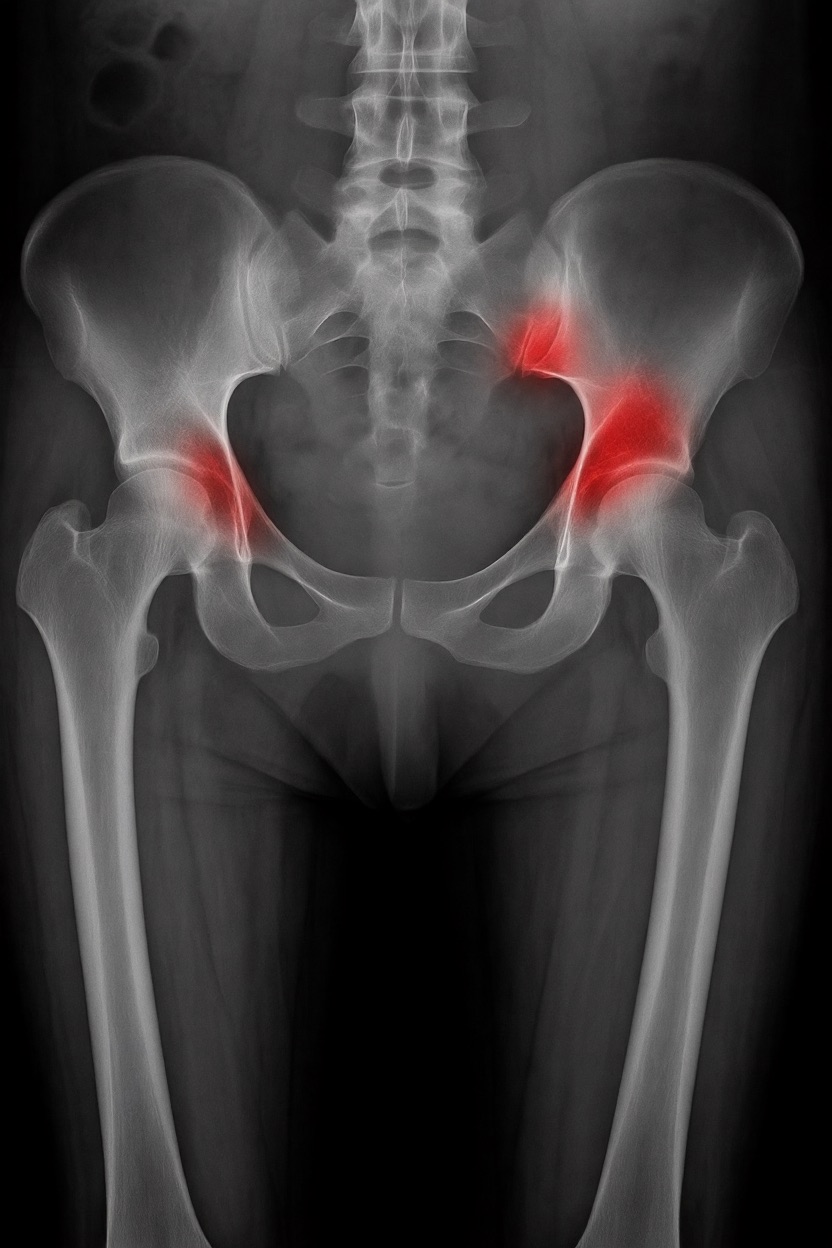

さらに攻撃的な設定(例:rk beta57、Denoise 1.0)では、**偽陽性100%、検出100%**という馬鹿げた結果に:すべてを赤で塗りつぶし、健常部もほぼすべて骨折と誤認する。未経験の目には区別がつかない。

有効な用途

- 医療画像におけるAIプロトタイプやテスト

- X線の「疑わしい」領域を視覚的に目立たせる(実験的・創造的アート、エキゾチックなツール xD)

- 感度 vs 偽陽性のバランスを実験するための教育的・実験的素材